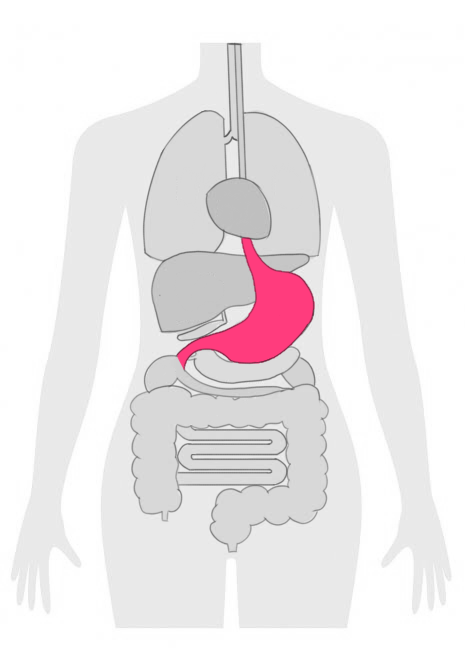

胃がんステージ4とは

胃がんステージ4は、胃がんの進行度を示すステージの中で最も進行している状態を指します。

このステージでは、がん細胞が胃の壁を超えて隣接する臓器やリンパ節に広がり、遠隔転移を起こしている場合が多いです。

胃がんの進行度は、TNM分類というシステムを用いて評価されます。

Tは腫瘍の大きさと侵入の深さ、Nはリンパ節への広がり、Mは遠隔転移の有無を示します。

胃がんは、その進行度に応じてステージ1からステージ4までの4つのステージに分類されます。

| 4 | がん細胞が胃の外側の層に広がり、遠隔転移を起こしている。 | 化学療法、放射線療法、手術、光免疫療法 |